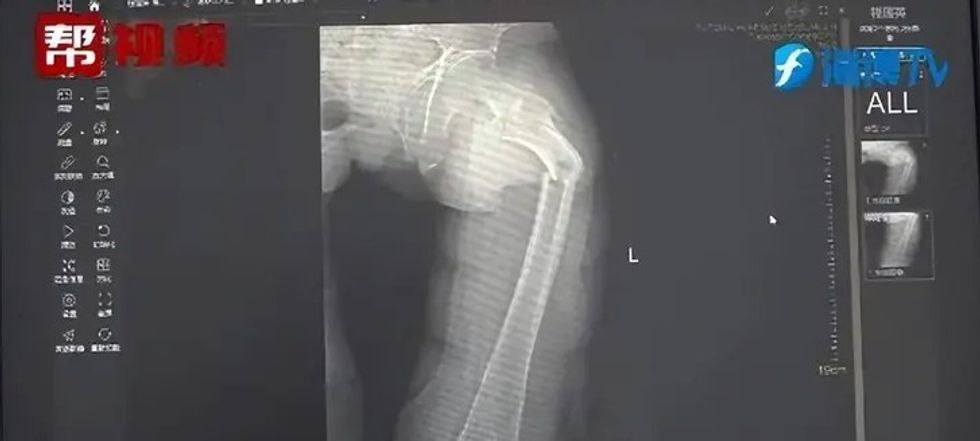

Një rreze X tregoi një frakturë të femurit, por historia nuk kishte kuptim për mjekët, raporton odditycentral.

Ata vendosën të hetojnë rastin dhe të marrin në pyetje pacientin rreth shëndetit në përgjithësi - zakonet, dietën dhe mënyrën e jetesës. Përveç kësaj, është bërë analiza e densitetit kockor, e cila ka dhënë rezultate shqetësuese.

Doli të ishte e ngjashme me densitetin kockor të një burri 80-vjeçar!